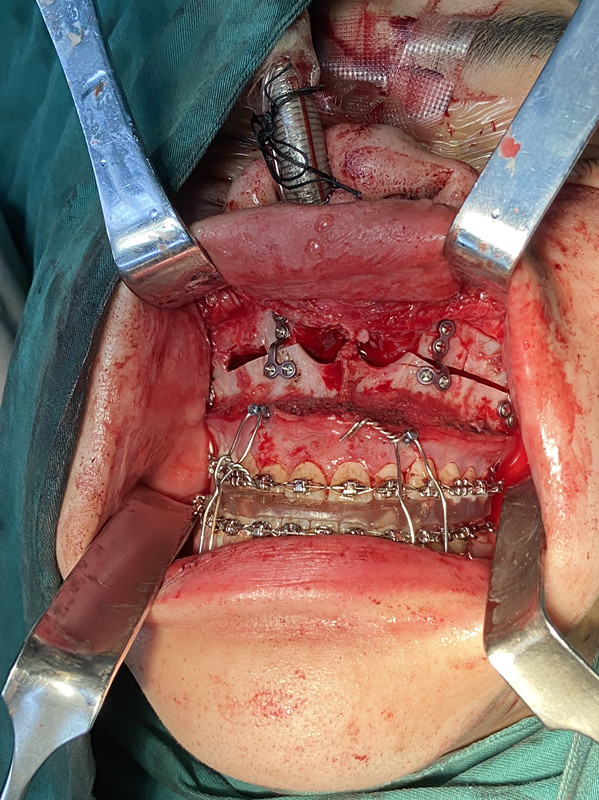

患者資料:男,21歲

術(shù)前診斷:上下頜骨發(fā)育異常(患者出生后,無(wú)明顯誘因出現(xiàn)下頜前突,上頜骨后縮,并且伴隨癥狀,癥狀無(wú)緩解)

手術(shù)方案:上頜骨 LefortⅠ型截骨術(shù)+下頜骨矢狀劈開(kāi)截骨術(shù)